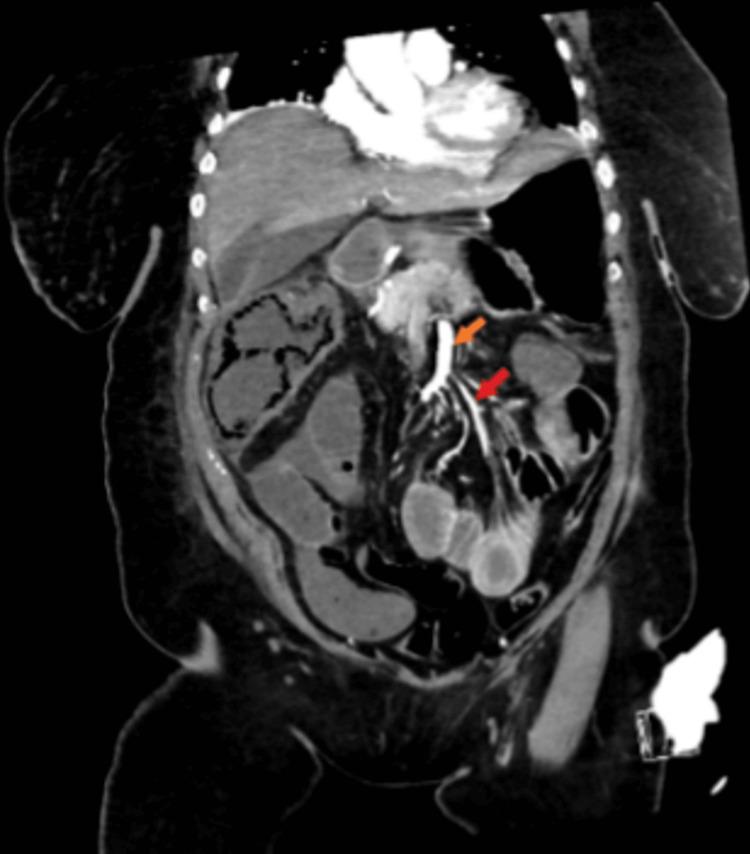

多枝梭菌血症伴因肠系膜上动脉和肠系膜下动脉闭塞继发的肠系膜缺血

Clostridium ramosum, despite being a common enteric bacterium, is not commonly identified as the cause of pathologic infections in humans. It was first identified by Veillion and Zuber in 1898 from a patient with pulmonary gangrene and appendicitis. After performing an extensive literature search of major databases, only a few cases of pathologic C. ramosum infection were found in the medical literature. In this piece of work, we add to existing research by presenting a case report of an 83-year-old female who presented with abdominal pain, fever, and shortness of breath, requiring ICU admission due to mesenteric ischemia and C. ramosum bacteremia.

多枝梭菌尽管是一种常见的肠道细菌,但在人类中并不常被确定为病理性感染的病因。它于1898年由韦利翁和祖伯首次从一名患有肺坏疽和阑尾炎的患者身上分离出来。在对主要数据库进行广泛的文献检索后,医学文献中仅发现了少数几例多枝梭菌病理性感染病例。在这项工作中,我们通过报告一例83岁女性病例来补充现有研究,该患者出现腹痛、发热和呼吸急促,因肠系膜缺血和多枝梭菌菌血症而需要入住重症监护病房。